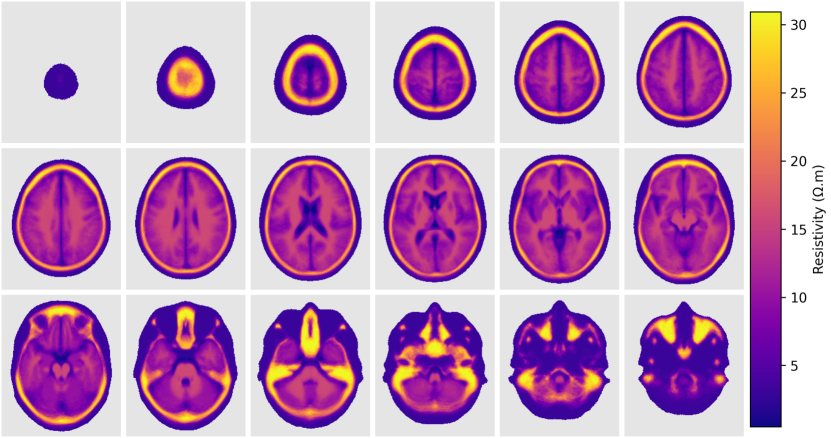

The static component of the atlas at 1 kHztimes1kilohertz1\text{\,}\mathrm{kHz} is presented in Figure 6. The figure shows transversal slices of the average (Figure 6(a)) and standard deviation (Figure 6(b)). It is possible to see high resistivity regions in the forehead, caused by the thick bone and the frontal sinus, in the zygomatic bones and the petrous part of the temporal bone in the base of the skull.

Refer to caption

(a)

(b)

Figure 6: Transversal slices of the static component of the atlas (resistivity) at 1 kHztimes1kilohertz1\text{\,}\mathrm{kHz}. (a) average; (b) standard deviation.

Figure 7 shows slices of the atlas built in terms of conductivity, resistivity, and relative permittivity and in different frequencies. The figure shows that the average resistivity and permittivity decrease with increases in frequency while conductivity increases. Although the average process tends to eliminate small features of the images, it is still possible to see small and thin structures inside the brain, like the longitudinal fissure, third and fourth ventricles and central canal.

Figure 7: Statistics of the atlas in different frequencies. (a) average; (b) standard deviation.